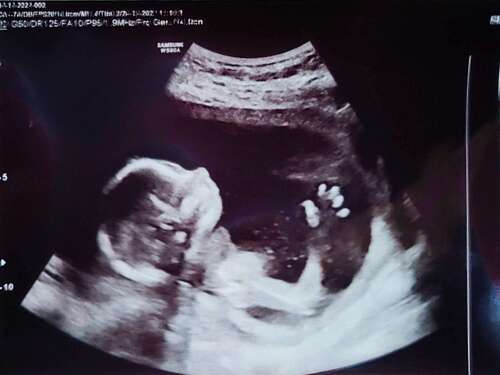

Afgelopen dinsdag de 13 weken echo gehad van ons 🫶🏼je. We hebben 2 hele mooie foto’s mee gekregen en de rest van de foto’s is op een usb stick gezet, eenmaal thuis aangekomen snel de usb stick in de laptop gestopt! Wat bleek de lieve dame had een kort filmpje gemaakt waarbij ons dotje aan het duimen was 🥰 zo verliefd!

Dit is mijn 13 weken echo met 13+4 dagen. Wat denken jullie wat het wordt q ...

Vandaag de 13 weken echo gehad van onze tweeling. Alles was goed en ze lagen er als fotomodelletjes bij dat we binnen een half uur weer buiten stonden 😅. Zo verliefd en blij ❤️ (bovenste foto is kindje 1 aan het drinken)